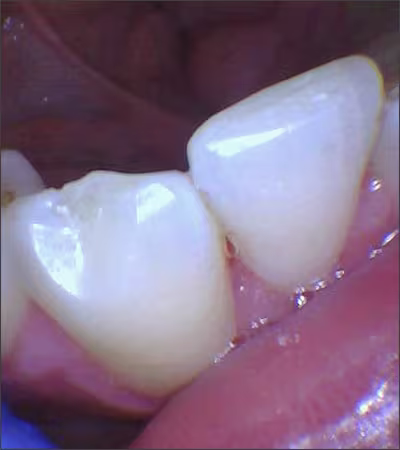

Attrition is the normal loss of tooth substance that results from friction by physiologic forces. 7Dental attrition is caused by tooth-to-tooth contact, resulting in loss of tooth tissue, usually starting at the incisal or occlusal surfaces. Clinical crown damage of the teeth can significantly thin the enamel structure, thus exposing the underlying structure called dentin (Figure 1). Dentin is softer and darker, increasing the risks of sensitivity, decay and discoloration. The etiology of dental attrition is multifactorial, with the most common cause being bruxism.

Figure 1.

Attrition exposing dentin on tooth #25.